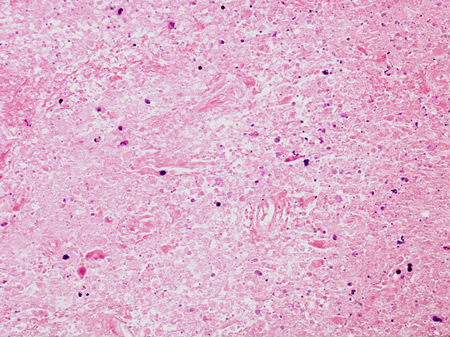

Biópsia do tálamo posterior do paciente com doença de Creutzfeldt-Jakob exibindo as mudanças espongiformes

Do acervo pessoal de Robert E. Schmidt; usado com permissão

Veja esta imagem em contexto nas seguintes seções: